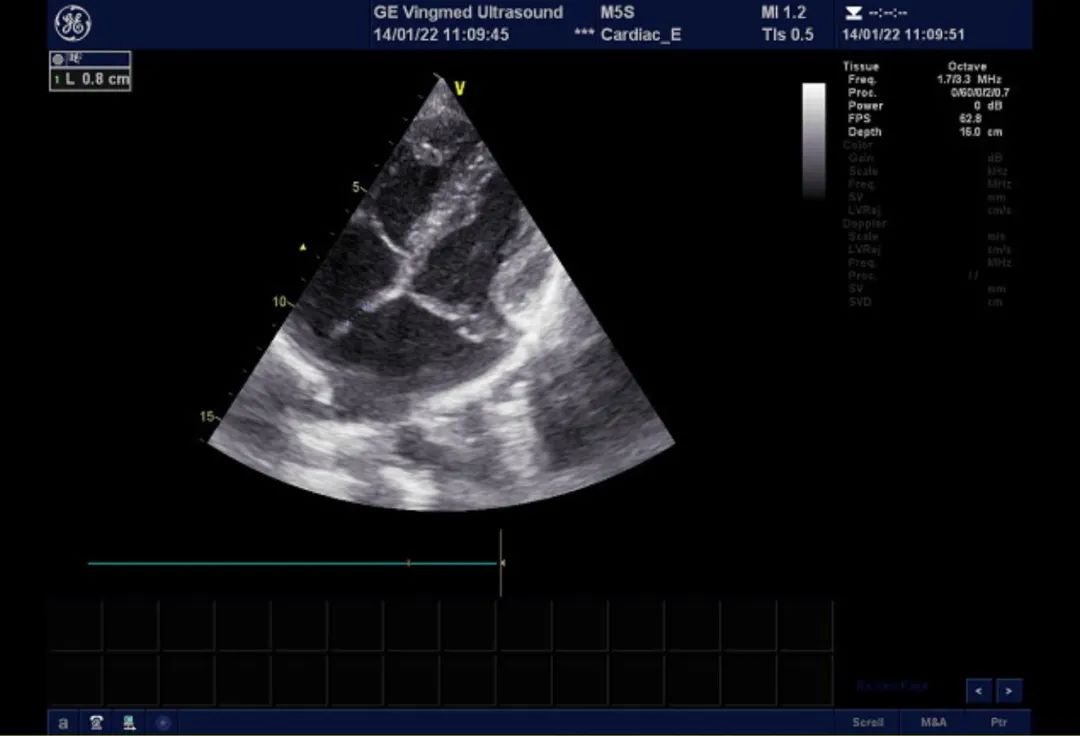

二尖瓣后叶脱垂,大量返流

双孔型房缺,分别为1cm及8mm大

术中食道超声提示二尖瓣瓣叶冗长,组织增厚,多处返流。提示barlow综合征可能。

术中食道超声监测